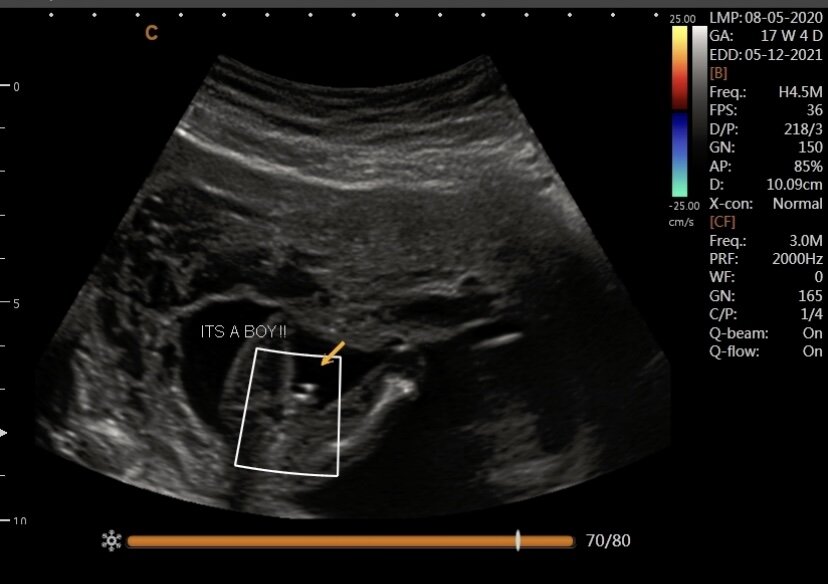

A regular 2-D ultrasound creates a cross-sectional view of your baby. This is the typical black and white image and may be done at any stage in pregnancy from 7 weeks and up. This is most often used for diagnostical ultrasound when you receive your anatomy scan. We use 2D for gender determination and our heartbeat package.